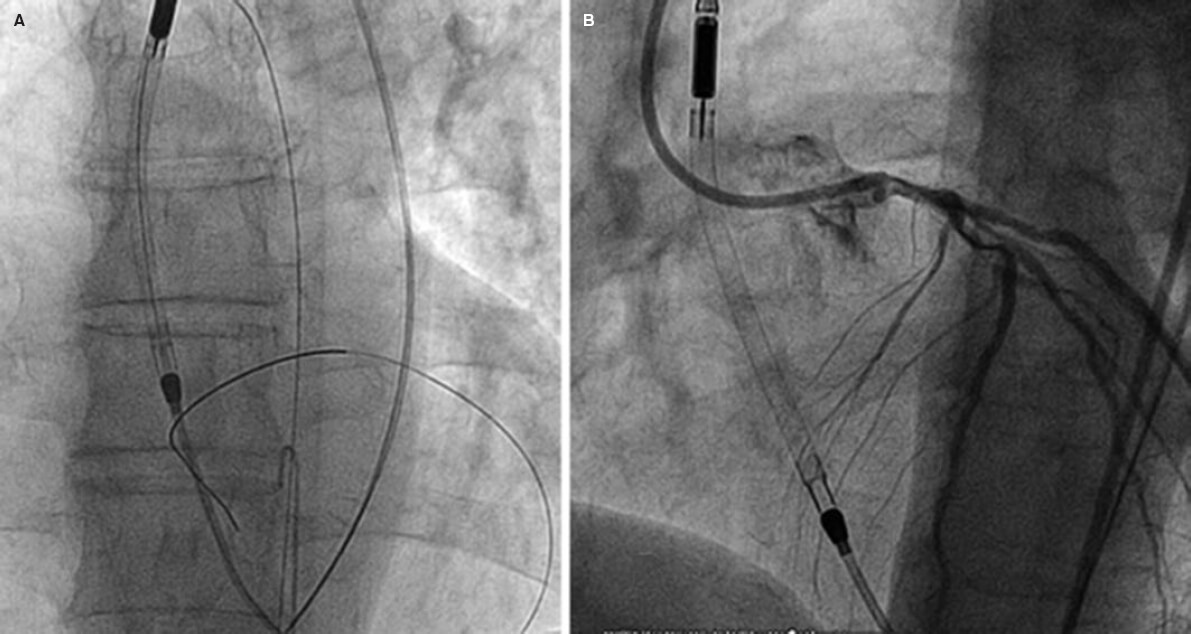

Los dispositivos tipo Impella (figura 2) emplean un catéter por vía femoral, que cruza la válvula aórtica y se aloja en el ventrículo izquierdo, donde succiona sangre oxigenada, que es devuelta hacia la aorta ascendente. Existen diferentes modelos: Impella 2.5, Impella CP e Impella 5.0, que proporcionan 2,5, 4 y 5 l/min de flujo, respectivamente.

Figura 2. Intervención coronaria percutánea de alto riesgo bajo soporte circulatorio con dispositivo Impella 2.5. En A y B se observa la localización correcta del dispositivo cruzando la válvula aórtica.